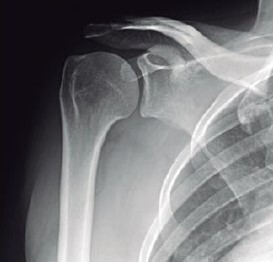

O exame de ombro, denominado de AP verdadeiro, é obtido com angulação do raio a 45° de medial para lateral, com o braço ao longo do corpo. Outra opção alternativa seria rodar o paciente até que a escápula fique encostada no filme e o raio incida perpendicularmente à escápula. Essa incidência tem como objetivo principal evidenciar a articulação glenoumeral e o espaço subacromial.

De acordo com a imagem é correto verificar que o posicionamento do paciente foi